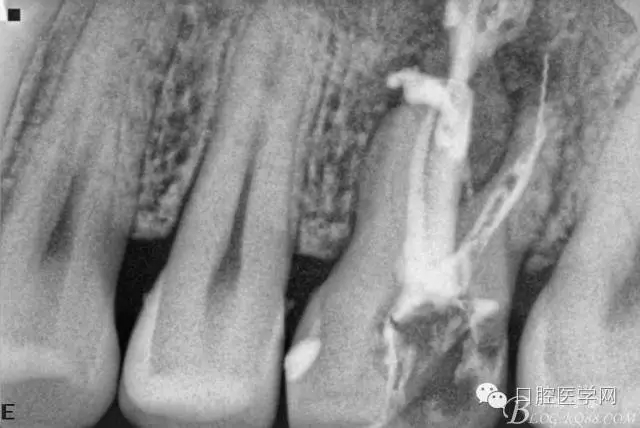

根充后三個(gè)月。

根充后四個(gè)月。根尖炎性陰影明顯減小,唯獨(dú)遺憾的是遠(yuǎn)頰根一斷針,不知后續(xù)如何,日后再行根尖手術(shù)吧。